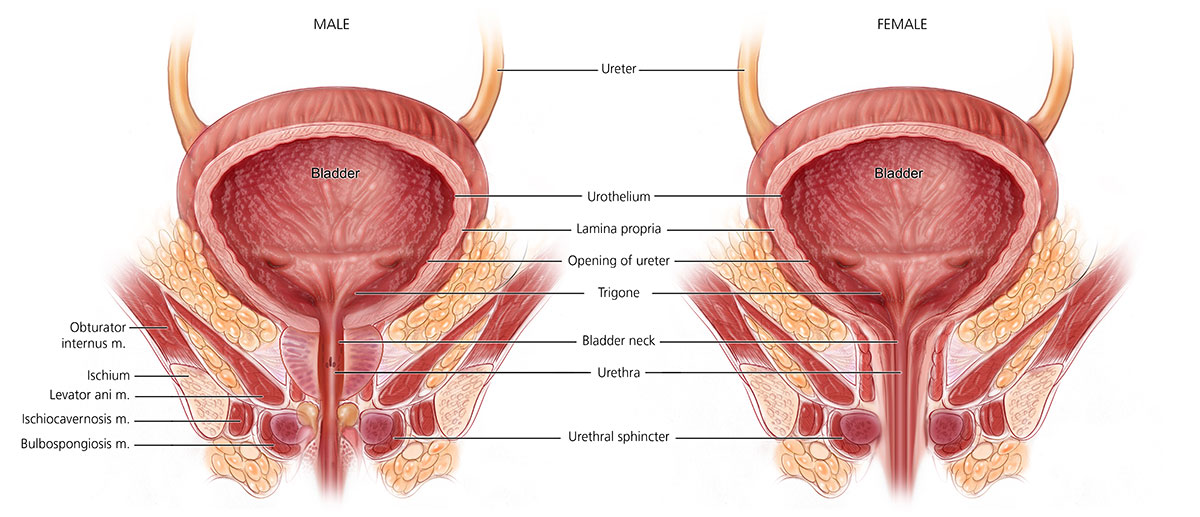

قیمت: 68٬000 تومان - دسته بندی فایل: پاورپوینت

قیمت: 68٬000 تومان - دسته بندی فایل: پاورپوینتپاورپوینت عضلات لگن در بانوان و بارداری

فروش ویژه پاور پوینت حرفه ای عضلات لگن در بانوان و بارداری با تخفیف استثنایی فقط 73 هزار تومان تعداد اسلاید: 38 اسلاید